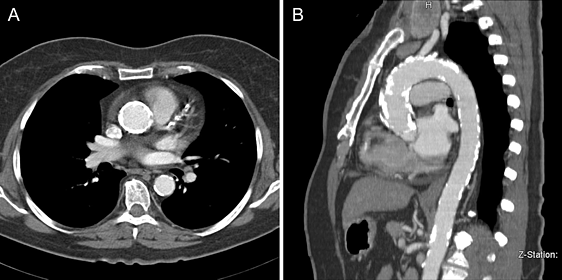

- МСКТ восходящей аорты с контрастированием – показано при постстенотическом расширении корня аорты;

Распространенная кальцификация аорты со стенозом клапана. Предпочтительнее транскатетерная замена клапана.

Хирургическое лечение приобретенных пороков сердца

Хирургическая коррекция аортального порока осуществляется с помощью его протезирования механическими, биологическими каркасными и бескаркасными протезами или криоконсервированными аллографтами.

У некоторых пациентов возможно выполнение реконструкции аортального клапана. В случаях узких аортальных колец для достижения оптимальной гемодинамики выполняется пластика корня аорты биологическим материалом.

Операции проводятся как из стандартного так и миниинвазивного доступа.